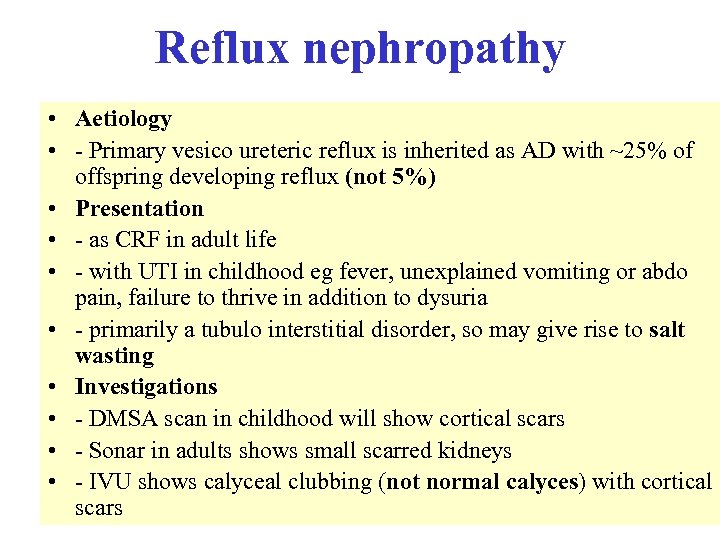

Reduced serum complement • • Occurs in: - SLE - infective endocarditis - post strep nephritis - shunt nephritis - cholesterol embolism - cryoglobulinaemia - MCGN types 1 and 2 • • Complement normal in FSGS, amyloidosis, Alports, anti GBM disease C 3 nephritic factor is an Ig. G auto antibody to the C 3 convertase of the alternative pathway of complement activation, found in both types of MCGN